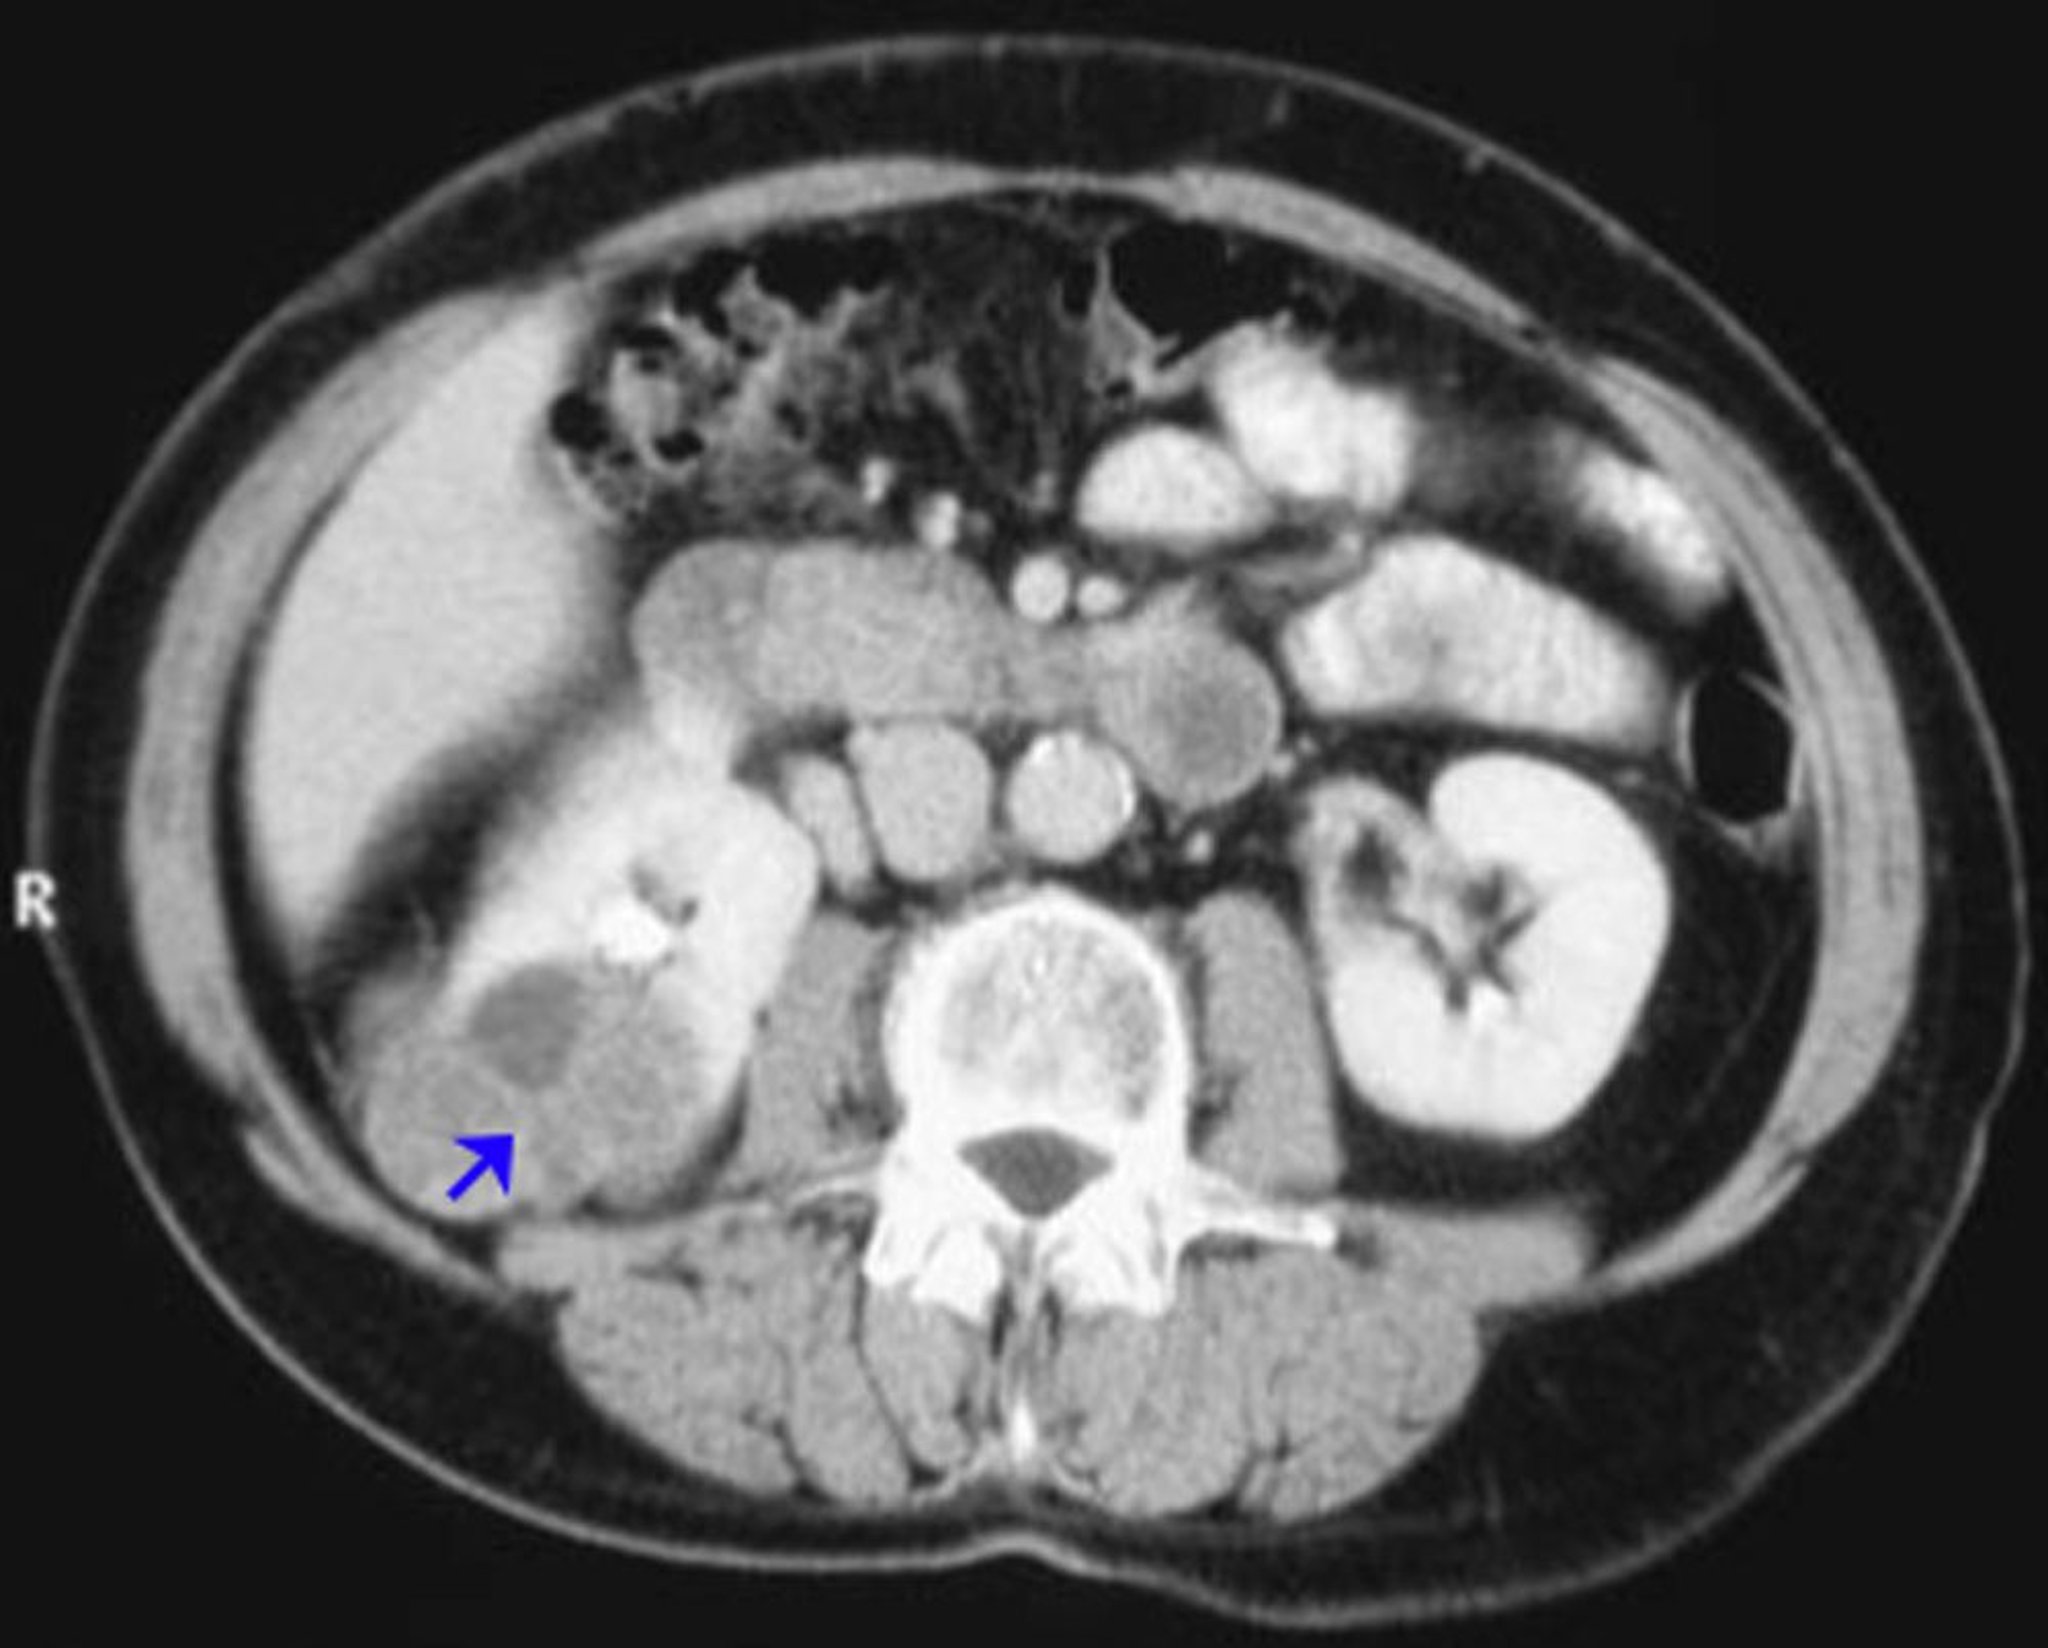

Renal Cell Carcinoma (Contrast CT Scan)

This image shows an example of a renal cell carcinoma of the right kidney (arrow) showing a poorly enhancing tumor.